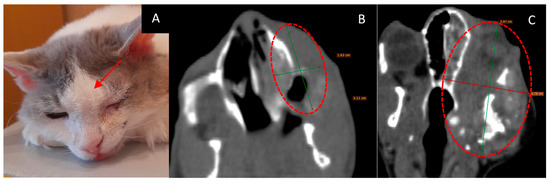

3.3. Male Cat “Sausage”

- Age: 6 years.

- Symptoms: impaired nasal breathing and nasal discharge.

- Tumor localization and size: left nasal area with bone destruction and regional lymphadenopathy. According to the CT scan, the tumor size was 33 × 26 × 26 mm.

- Treatment other than GdNCT: standard X-ray radiotherapy with doses of 35.4 Gy for the tumor (6 sessions) and 30 Gy for the lymph nodes (6 sessions). The outcome of that treatment was tumor recurrence.

- Pathological diagnosis: squamous cell carcinoma.

- The course of the disease after GdNCT: after irradiation, the animal was lethargic and had facial edema and a necrotic area (circled in the photo) with exudate. Two months after GdNCT, there were signs of tumor recurrence in the back of the nose, upper jaw, and corner of the eye (Figure 3).